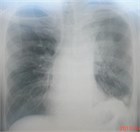

1. 肺がんの危険因子が多い患者では無症状でも胸部CTなど詳細な陰影の質的な評価と単純X線写真でとらえられないその他の異常所見の確認もする(推奨度1)

1. 肺がんの危険因子の乏しい患者での3cm以下の石灰化を伴う結節影は良性のことが多い(推奨度1)

1. 迅速に出現した結節影は円形肺炎を考える(推奨度1)